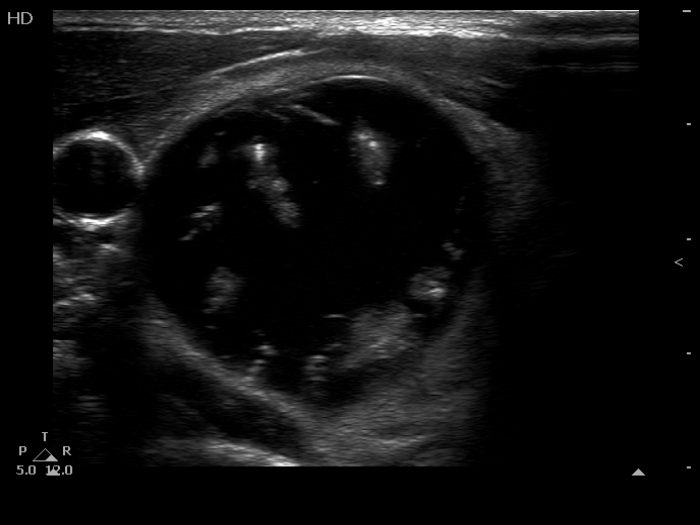

The composition of the nodule - case 1511 (ultrasonographic picture 2)

Right lobe, another transverse scan. Ragged echonormal tissue fragments float within the deeply hypoechogenic background. One of the echogenic figures cannot be categorized other than comet tail artifact.